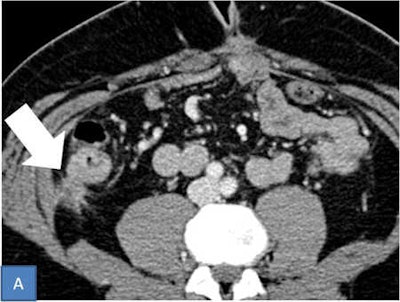

"Radiologists must specify every site of peritoneal carcinomatosis in order to provide a staging as detailed as possible," concluded Ciolina. "The best rule to make a good report is to carefully check the surface of the bodies covered by the peritoneal layer, peritoneal ligaments, and peritoneal spaces that surround them."